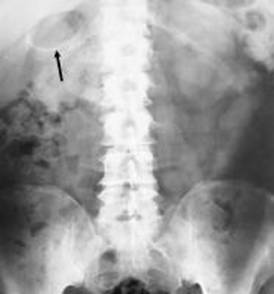

1.3.3-Radiogramma diretto dell'addome

L'esame radiografico dell'addome viene effettuato principalmente per escludere alcune diagnosi differenziali. Tuttavia vi sono alcuni segni radiografici indicativi di colecistite acuta:

Dilatazione di anse intestinali (segno di un possibile ileo paralitico);

Colecisti a porcellana (segno di una già pregressa colecistite cronica);

Possibile visualizzazione di un calcolo in sede colecistica (perché ciò avvenga il calcolo deve essere radiopaco e ciò avviene in circa il 15-20% dei pazienti)

Gas nella parete della colecisti (segno indicativo di colecistite enfisematosa). 9 ,10

Fig .1 Radiogramma diretto di paziente con colecistite enfisematosa

si noti la presenza di aria nella parete della colecisti

Fig 2 radiogramma diretto dell'addome. Numerose formazioni all'ipocondrio di destra